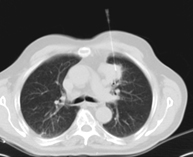

- TC Tórax

Prueba diagnóstica que consiste en obtener imágenes del tórax de alta definición anatómica (pulmones, corazón, mediastino, grandes vasos, caja torácica, etc.) mediante el empleo de un equipo de TC (Tomografía Computarizada). Dichas imágenes se estudian posteriormente en una estación de trabajo que permite reconstrucciones bidimendionales en diferentes planos del espacio y también reconstrucciones 3D (volumétricas). Algunos estudios requieren el empleo de contraste yodado para mejorar la definición de las imágenes. - Angio-TC Aorta torácica